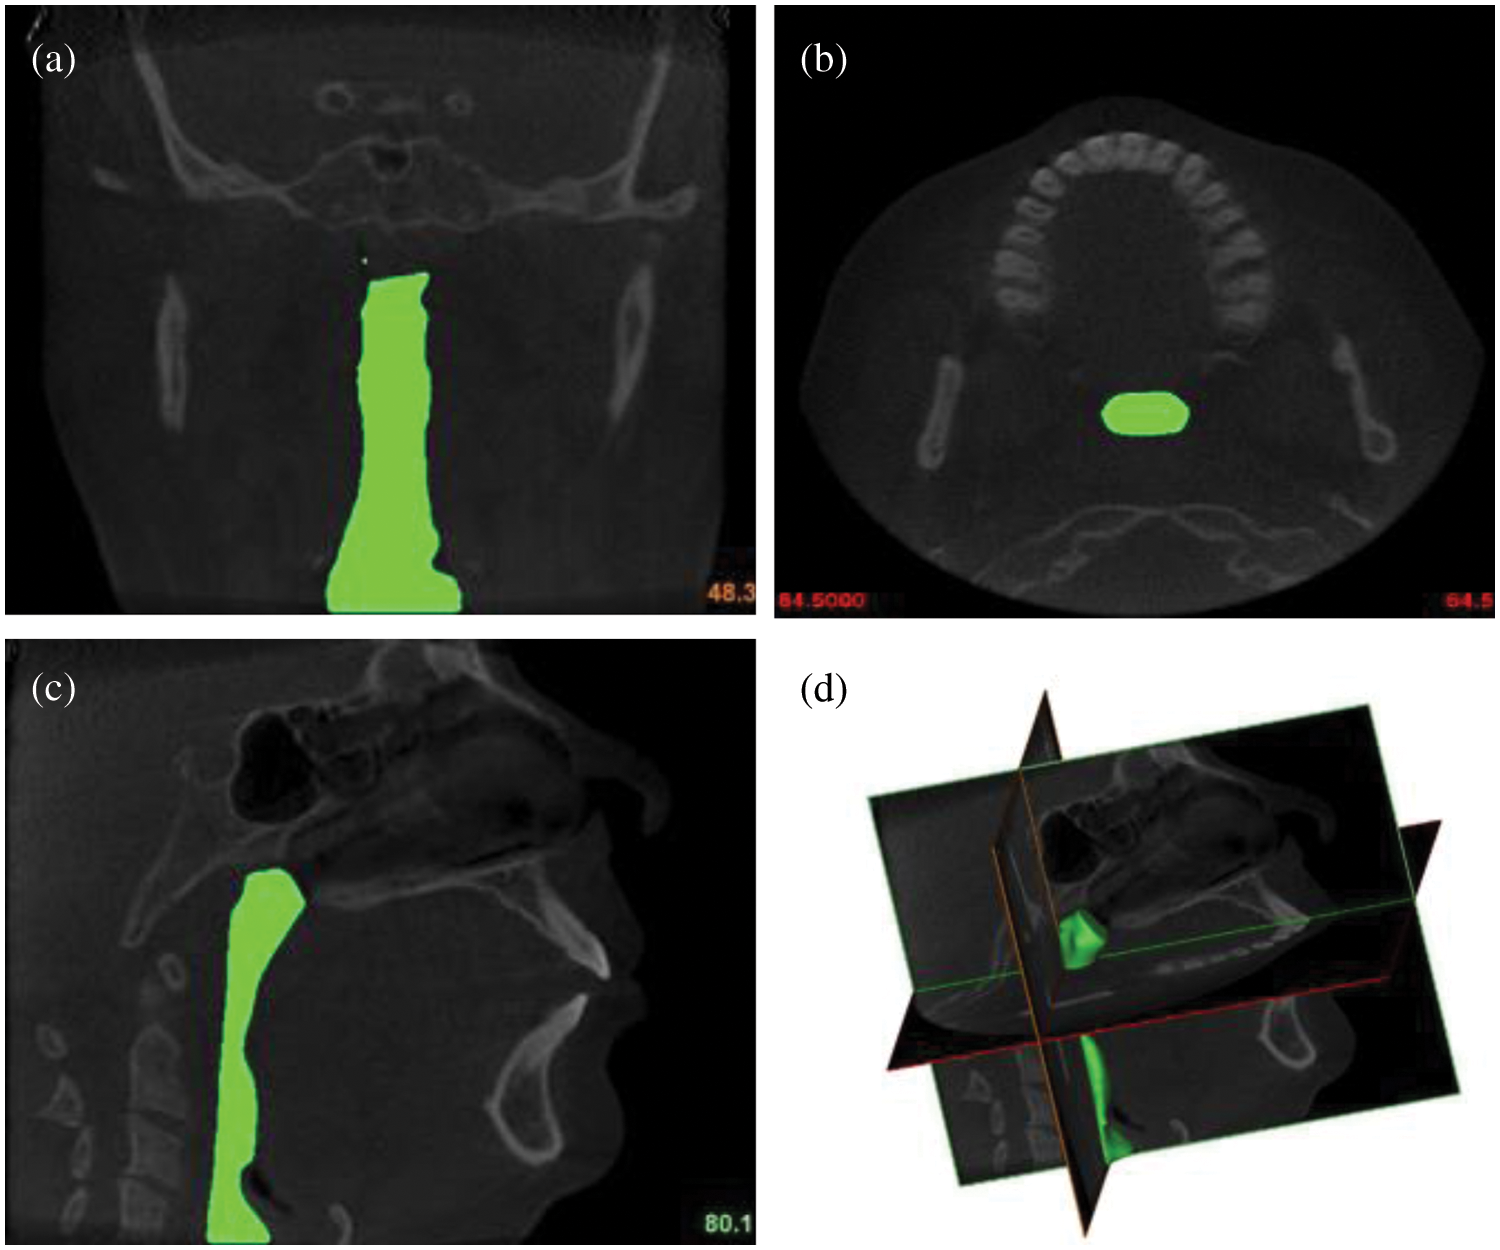

All procedures in this study were conducted in accordance with the Universiti Malaysia Perlis Research Ethics Committee, Perlis, Malaysia-UniMAP/PTNC(P&I)/JKETIKA (10/11/2021) approved protocols. Written informed consents were received from all the patients, and the study was conducted according to the tenets of the Declaration of Helsinki for research involving human subjects. The upper airway geometry is extracted from CT scan images of 24-year-old female nonsmoking OSA patient volunteers. The BMI of the patient is 70.3 kg/m2, and the AHI is 99.5. The summarized characteristics of the OSA subject that were selected for the conduction of the upper airway CT scan. According to previous works, the focus of the subject of interest was decided to be from the nostril until the pharyngeal [13]. A total of 431 frames with 0.3 mm of slice thickness covering the upper airway CT scan of the subject were performed using an i-CAT Cone Beam 3D Dental Imaging System (version 3.1.62 supplied by Imaging Science International, Hatfield, USA), as shown in Fig. 2.

Figure 2: The airways of OSA patient: (a) coronal view; (b) axial view; (c) sagittal view; and (d) 3D volume pharyngeal airway

The airway boundary is identified from the CT scan images via a threshold based on the intensity of the grey image. The thresholding method divides images into sub-images and then determines the threshold value for each portion in order to find different threshold values for various parts of the images. The results of the thresholding are then combined for each component of the image. This technique splits an image into vertical and horizontal parts containing a section of the object’s background. Finally, interpolation is required to achieve the desired outcomes [21]. The images were captured while the patient was awake and lying down with their face upward, as explained in the works of Chan et al. [22]. Each CT scan has 534 pixels × 534 pixels, and the pixel spacing is 0.3 mm × 0.3 mm. A series of CT scan images were stored in a Digital Imaging and Communications in Medicine (DICOM) format. Then, the DICOM images were imported into a three-dimensional (3D) medical image processing MIMICS software (version 15.0; Materialise, Leuven, Belgium). The image segmentation of the upper airway was carried out to identify the 3D airway region based on the pixel value (Hounsfield unit) from the DICOM image series. The airway surface model was generated using segment airway in pulmonary function test, as shown in Fig. 2. Then, the 3D volume of the pharyngeal airway was created and exported for the 3D model mesh generation.